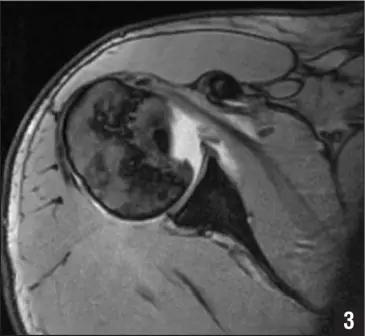

Hill-Sachs 损伤的 MR 片(来源:Hill-Sachs Injuries of the Shoulder)